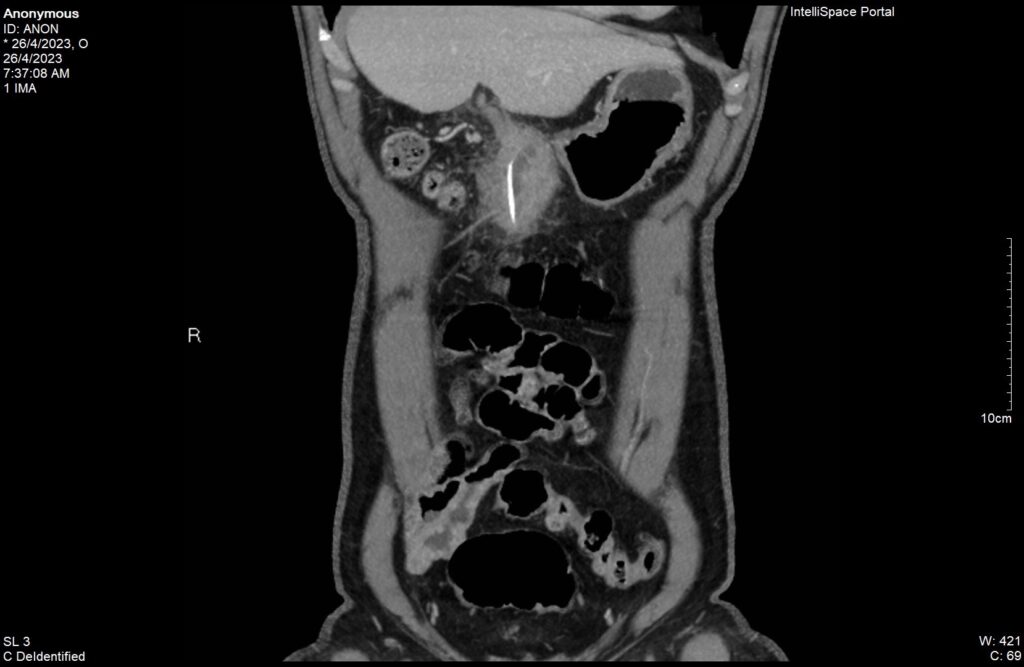

Phim CT ghi nhận dị vật trong đường tiêu hóa

Dù đã tự uống thuốc giảm đau nhưng không thuyên giảm, cơn đau càng ngày càng tăng nên nhập viện cấp cứu. ThS. BS Phạm Hoàng Thiên- Trưởng Khoa Cấp cứu, BV Hoàn Mỹ Sài Gòn người trực tiếp tiếp nhận bệnh cho biết “Qua thăm khám ban đầu tại khoa Cấp cứu, nghi ngờ có khối áp xe ổ bụng trên người bệnh có các bệnh mạn tính nặng như tăng huyết áp, bệnh tim thiếu máu cục bộ, đái tháo đường, suy thượng thận và viêm dạ dày, chúng tôi tiến hành cho người bệnh chụp CT bụng và vùng chậu bằng thuốc cản quang. Kết quả cho thấy người bệnh bị áp xe ổ bụng vùng trước hang môn vị dạ dày do có dị vật dạng que thẳng dài 40mm, đường kính ngang 2mm nghi đâm xuyên thành dạ dày ra ngoài”